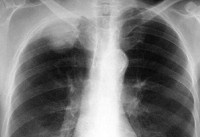

Рентгенография легких помогает выявить затемнение в области верхней борозды, утолщение плевры на верхушке легкого; часто обнаруживается деструкция I-III ребер, ниж­них шейных и верхних грудных позвонков. С помощью КТ или МРТ легких определяется степень инвазии опухоли в сосуды, лимфоузлы, ребра, позвонки, ткани грудной стенки. Эти сведения крайне важны для прогнозирования операбельности при раке Панкоста. Для оценки вовлеченности кровеносных сосудов возможно проведение артерио- или флебографии, либо контрастной компьютерной томографии.